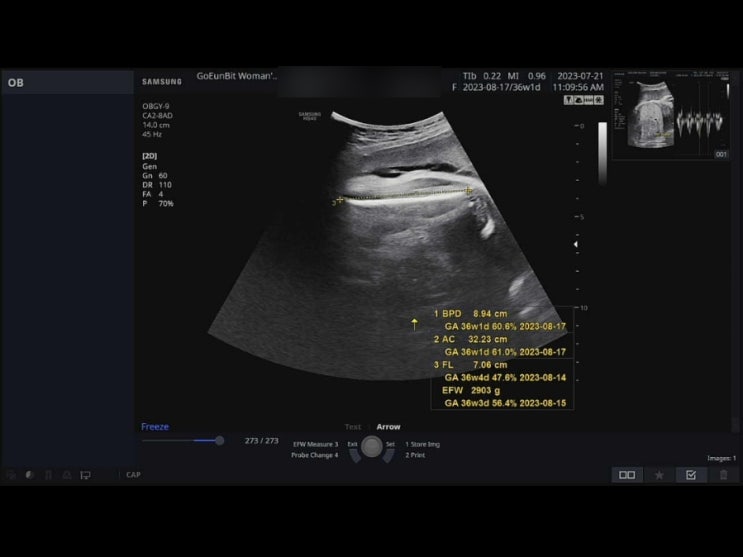

[36주1일] 정기검진│ 임신소양증으로 인한 주사처방

2023.07.21 지난 검진에 이어 다음번 검진은 원래 7월 마지막주였으나, 좀더 앞당겨서 방문을 했어요. 지난...